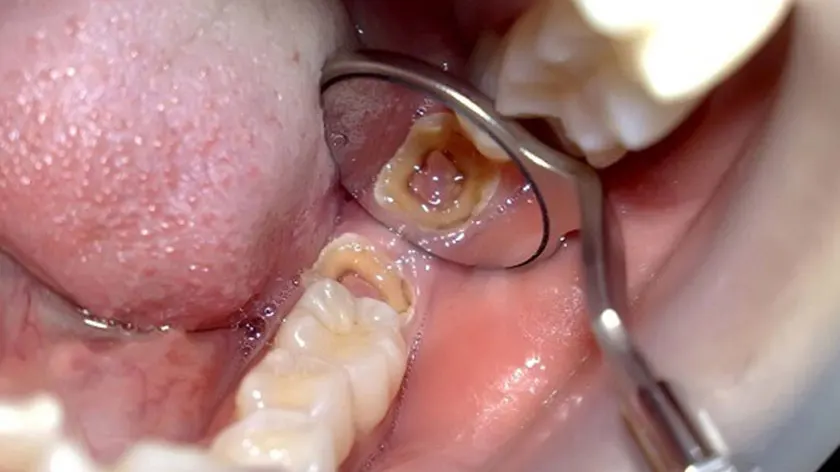

- Bác sĩ sẽ quan sát, kiểm tra khoang miệng và răng của người bệnh.

- Kiểm tra nướu răng bằng các dụng cụ nha khoa chuyên biệt.

- Chụp X-quang để chuẩn đoán mức độ sâu răng.